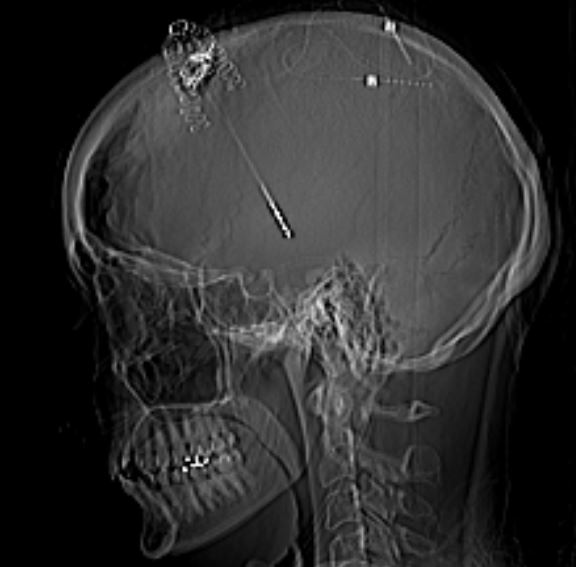

Below is my CT scan right after the 8 hour surgery. The leads were coiled up under my scalp and will be connected in the next surgery. You can see them towards the back of my head.